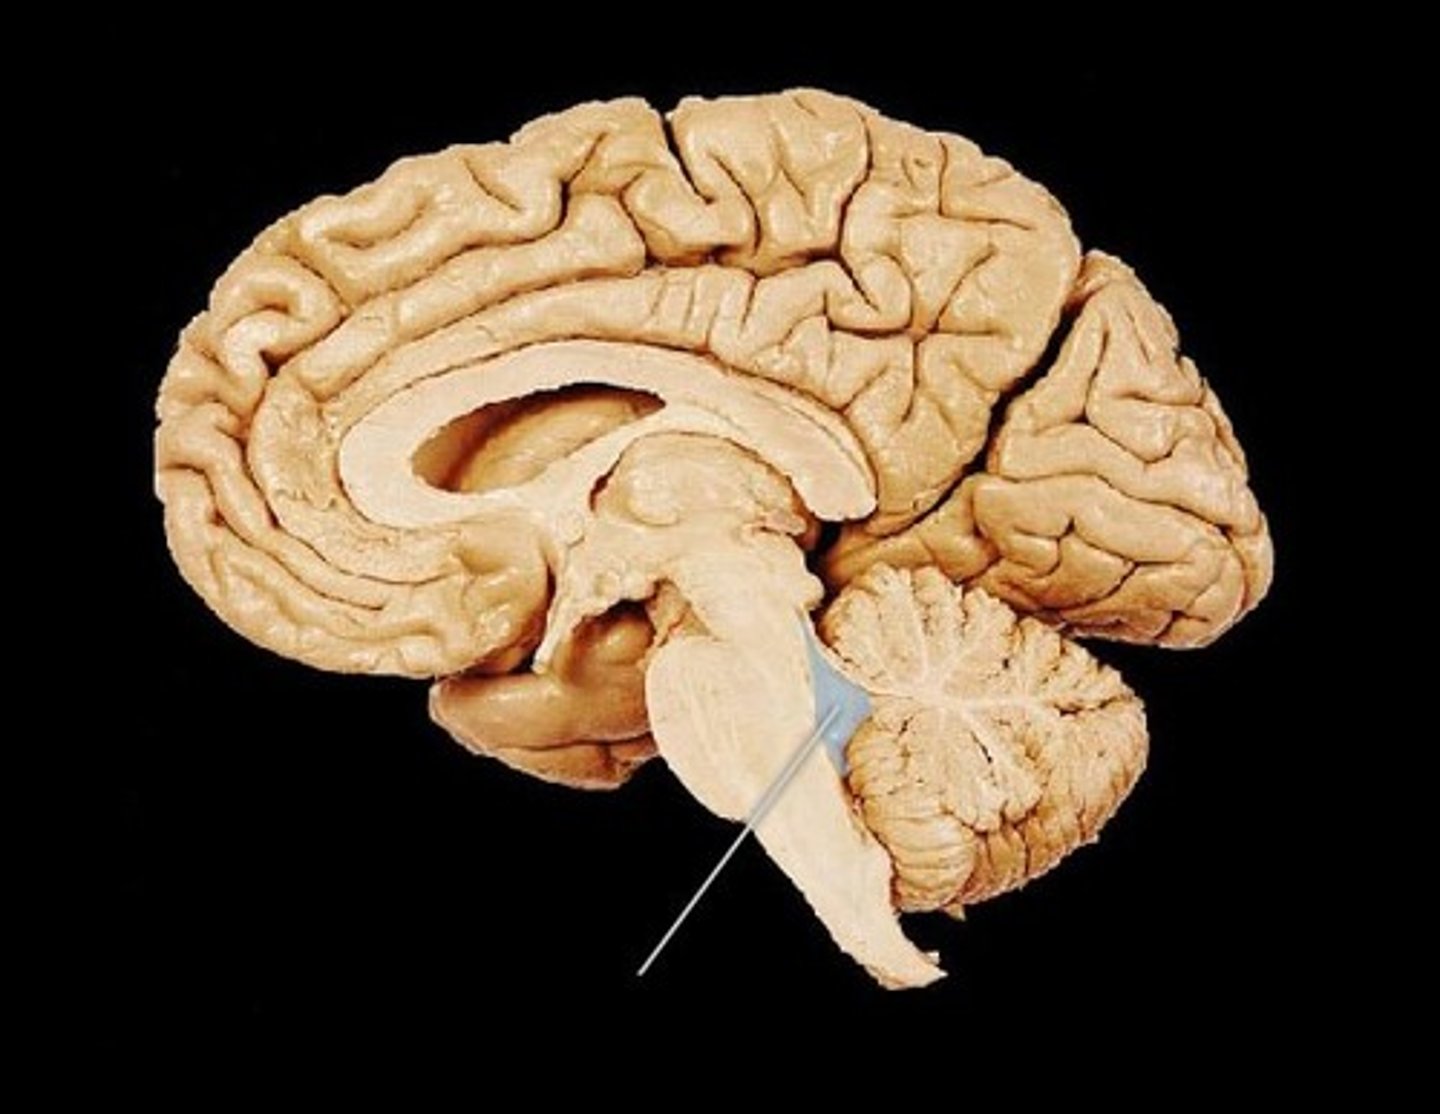

brainstem

cerebellum

cerebrum

medulla oblongata

midbrain

pons

thalamus

corpus callosum

fornix

cerebral aqueduct (brainstem)

corpora quadrigemina (brainstem)

fourth ventricle

hypophysis (pituitary gland)

infundibulum

intermediate mass of thalamus

pineal gland

third ventricle